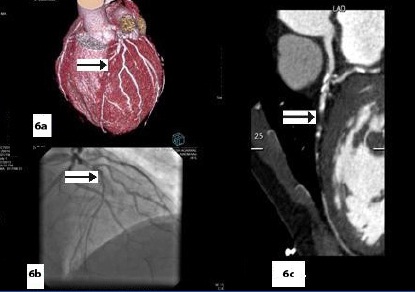

Five patients (12.5 %) had normal angiograms [Table/Fig-2,2b,3,3b], six (15%) had non-significant disease [Table/Fig-4,4b,5a,5b] and 29 patients (72.5%, 26 male & 3 female) had significant disease [Table/Fig-6a,6b],[7a,7band8] on CT coronary angiography, which was also proved on invasive angiography [Table/Fig-9]. The incidence of significant coronary detected was highest in age group of 41-60 years [Table/Fig-10].

(VRT) & (MPR) images show near complete stenosis of proximal LAD on CT coronary angiography (arrow)

Catheter angiography image showing complete occlusion of LAD in \ proximal segment (arrow)